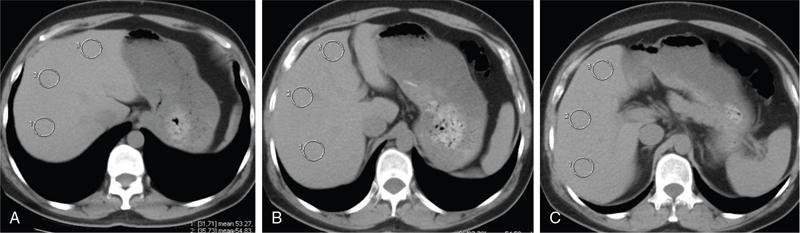

Excessive triglyceride accumulation within hepatocytes is defined as hepatic steatosis. Major conditions associated with hepatic steatosis include alcoholic fatty liver disease (AFLD) and nonalcoholic fatty liver disease (NAFLD). Causes of hepatic steatosis are discussed in Table 9.10.3. NAFLD is the most common form of hepatic steatosis and discussed in detail below. Up to 90% of patients with chronic alcoholic intake have fatty liver. Those with pure AFLD have a 10% risk of progressing to cirrhosis. Consumption of 30 g ethanol/day shows increased risk of chronic liver disease and cirrhosis. Other risk factors include female sex, obesity, cigarette smoking, obesity and associated risk factors. These factors are divided into 2 main categories which can cause fatty liver: inborn errors of metabolism and acquired metabolic disorders. Inborn errors of metabolism include abetalipoproteinemia, galactosemia, glycogen storage disease, hereditary fructose intolerance, homocystinuria and Wilson disease. Inflammatory bowel disease, jejunoileal bypass, malnutrition, starvation and total parenteral nutrition are acquired metabolic factors associated with increased risk. Chronic HCV infection, is associated with hepatic steatosis, with prevalence of 40%–80%. Hepatic steatosis can be seen as an adverse reaction to some medications such as tetracycline, valproic acid, some of chemotherapeutic agents, dexamethasone, amiodarone, methotrexate, tamoxifen and acetylsalicylic acid. Either microvesicular or macrovesicular steatosis can be observed in drug-induced hepatic steatosis. It generally occurs with therapy lasting several weeks or months and is reversible after discontinuation. The leading cause of hepatic steatosis in paediatric population is NAFLD. Six per cent of these patients develop cirrhosis and end-stage disease. Other less common causes include starvation and malnutrition, drugs (glucocorticoids, oestrogens, tetracyclines, and methotrexate), intoxications (carbon tetrachloride, organic phosphates, organic solvents, and alcohol), metabolic disorders, hepatitis C infection, and total parenteral nutrition. NAFLD is defined as steatosis affecting >5% of hepatocytes in the absence of a secondary cause. NAFLD represents a spectrum of disease, ranging from simple steatosis to steatohepatitis through to fibrosis and cirrhosis and in some cases hepatocellular carcinoma. NAFLD is a growing epidemic worldwide in part due to obesity and insulin resistance leading to liver accumulation of triglycerides and free fatty acids. Nonalcoholic steatohepatitis (NASH) is defined by histologic terms as a necroinflammatory process whereby the liver cells become injured in a background of steatosis. 20% of patients with NAFL progress to NASH, which progresses to fibrosis and cirrhosis over a 15-year time period (Fig. 9.10.3). The definition of NAFLD requires imaging or histology evidence of steatosis and no causes for secondary hepatic fat accumulation like significant alcohol intake, drugs or hereditary disorders (Table 9.10.4). The incidence of NAFLD ranges from 20% to 30% in Western countries and 5%–18% in Asia. As it currently stands, NAFLD represents the second most common reason to be listed for a liver transplant. The prevalence of NAFLD is higher in patients with obesity, diabetes, and patients with hyperlipidaemia. Prevalence increase with age from less than 20% at age 20 to more than 40% over 60 years of age. Males show a higher risk for progression to NASH and fibrosis (Table 9.10.5). Up to 90% of patients with NAFLD have simple steatosis, and about 30% of patients with NAFL develop NASH, and in again about 30%–40% of NASH patients the disease progresses to manifest fibrosis and cirrhosis NAFLD related cirrhosis has a 10-year mortality of 25% and a 5% chance of developing end-stage liver disease and HCC. The theory implicated in the pathogenesis of NAFLD is the two-hit theory. Insulin resistance, enhanced dietary influx and increased hepatic lipogenesis leading to accumulation of triglycerides (TG) and FFA in the hepatocytes is the first hit. The lipid peroxidation, mitochondrial dysfunction and inflammation resulting in hepatocyte damage and development of liver fibrosis is the second hit. The stages of NAFLD on histology range from steatosis initially to hepatic fibrosis in late stages. In the steatotic stage large (macro-) and small (micro-) vesicles of fat, predominately triglycerides, accumulate within hepatocytes. The affected parenchyma is divided into thirds: 5%–33%, 34%–66% and >66% and graded as mild, moderate and respectively. Ballooned hepatocytes with accompanied steatosis and inflammation are characteristic of the steatohepatitis stage. Fibrosis has a characteristic appearance with early lesions showing a perisinusoidal deposition followed by periportal fibrosis which progresses to bridging. Raised GGT is the most common liver enzyme elevated in NAFLD. Transaminases are within normal range in 80% patients. No specific blood tests can diagnose NAFLD. Liver biopsy has remained the gold standard for diagnosis and quantification of liver fat. Drawbacks, however, include invasive nature, sampling error and procedure related complications like bleeding. Various imaging techniques are currently available in diagnosing and quantifying liver fat. MRI in particular proton density imaging and MR Spectroscopy have revolutionized imaging of fatty liver. Normal liver parenchyma is the same as or slightly more echogenic than the adjacent kidney and spleen. Fat deposition leads to increased echogenicity of liver. Decreased beam attenuation in patients with fatty change leads to poor visualization of structures such as intrahepatic vessels, bile ducts and liver lesions and in severe cases diaphragm (Table 9.10.6). Fatty liver can be graded on USG as: US has a fair accuracy of detecting the moderate to severe hepatic steatosis with sensitivity of about 90% and specificity of about 95% for patients without concomitant chronic liver disease. Ultrasound is observer and equipment dependent. Confounding factors such as large body hiatus may lead to overestimation of hepatic steatosis due to beam attenuation by overlying fat. Conditions like fibrosis, inflammation can affect interpretation. The ratio between the mean brightness level of liver and right kidney is called the Hepatorenal sonographic index. A cut off of 1.49 has a high sensitivity and specificity for diagnosis of steatosis >5%. The main advantages of CT for assessing steatosis are relatively fast acquisition, ease of performance, and quantitative results. Estimation of fatty liver is done on non-contrast enhanced images. The normal liver density is around 60 HU, which is approximately 10 HU higher than normal spleen. Fat accumulation in the liver manifests as proportionate decrease in density. Both the absolute and relative (to the spleen) values are used to characterize steatosis; a cut-off value of 40 HU has been suggested to predict fat content greater than 30% (Figs. 9.10.6 and 9.10.7) Attenuation difference between liver and spleen on unenhanced CT scan is a commonly used quantitative parameter to evaluate hepatic steatosis. This avoids errors in attenuation value measurement from different CT scanners and different reconstruction algorithms. Normal liver parenchymal attenuation on nonenhanced CT is slightly higher than the spleen. Liver attenuation progressively decreases as percentage steatosis increases (Table 9.10.7) (Fig. 9.10.8) Methods of liver fat quantification on CT have been discussed in details in chapter on liver transplant. Limited diagnostic accuracy for detecting mild degree hepatic steatosis is one of major drawback of CT. Disorders causing hyperdensity of liver such as iron, glycogen deposition can lead to errors in interpretation. The concomitant presence of iron and fat may not be accurately diagnosed on CT. Low CT density values may also be caused by oedema and inflammation. Likewise, the spleen is an imperfect reference standard as it can be affected by haemosiderosis and haemochromatosis in a small minority of patients. Dual-energy CT with its ability to perform material decomposition is more accurate in quantifying hepatic steatosis and allows staging of fibrosis. Imaging is done with two different energies (typically 80 kVp and 140 kVp). DECT has the potential to quantitate liver fat content independent of ROI (region of interest) placement. Magnetic resonance imaging (MRI) is presently the most accurate imaging modality for the evaluation of hepatic steatosis. Several different methods have been developed and introduced in MRI for the evaluation of hepatic steatosis. In this technique typically, two gradient echoes are acquired, one employing a TE in which the water peak (4.7 ppm) and the dominant fat peak (1.3 ppm) are ‘out of phase’ and hence subtractive (SOP), and the other using a TE in which the two peaks are ‘in phase’ and therefore additive (SIP). Because two echoes are acquired, this is often called ‘dual-phase’ or ‘dual echo’ imaging. Fat Signal Percentage is calculated as [SIP – SOP]/[2 × SIP] ×100. The dynamic range of magnitude based chemical shift techniques has typically a 0%–50% signal fat-fraction (Fig. 9.10.9) This technique uses both magnitude and phase information from three or more images acquired at different echo times appropriate for more accurate separation of water and fat signals as against only magnitude information in dual-echo. These methods provide estimates of fat fraction with a dynamic range of 0%–100%. Proton density Fat fraction (PDFF) is calculated as Sf/(Sw + Sf) where Sw = SI of the water component, Sf = SI of the fat component. PDFF specifically reflects the concentration of triglycerides in the hepatocytes as lipids within the other structures such as cell membranes and organelles are occult. Sensitivity up to 96% and specificity up to 100% for detecting any degree of steatosis have been reported. A fat-fraction threshold of 5.56% is commonly used to define steatosis; however, the optimal cut-off value still needs to be defined (Figs. 9.10.10 and 9.10.11). MRS can directly measure the chemical composition within tissue based on the frequency composition of the signal originated from the voxel of interest. Water proton peak appears as a single peak at 4.7 ppm, whereas fat peaks appear as multiple peaks around 1.3 ppm. PDFF can be calculated as the ratio of the sum of the signal intensities derived from the protons in fat divided by the sum of the signal intensities originated from the protons in both fat and water (Fig. 9.10.12). TABLE 9.10.8 MRS data are usually obtained from a single voxel manually placed in the liver parenchyma usually right posterior segment of the liver. Reported MRS sensitivities and specificities for detection of mild hepatic steatosis are 80.0%–91.0% and 80.2%–87.0%, respectively, outperforming CT and US. MRS can also provide excellent reproducibility of measurement. It is also unaffected by confounding factors like fibrosis, iron overload and glycogen. Small sample volume usually less than 3 × 3 × 3 cm3 is a major limitation of MRS, particularly in patients with uneven fatty change. Despite these practical limitations, MRS is considered to be the gold standard MR method for hepatic fat quantification. This is the most frequently encountered pattern and considering the homogenous involvement poses no diagnostic dilemma. Focal fat deposition and focal sparing in diffuse fatty liver are less common. These usually occur in specific locations like adjacent to falciform ligament or ligamentum venosum, in portal hepatis or gallbladder fossa. Imaging findings are suggestive of fatty pseudolesions rather than true masses. Occurrence in characteristic locations, absence of mass effect on vessels and structures, geographic configuration and contrast enhancement similar to or less than adjacent liver (Fig. 9.10.13). Fat deposition around insulinoma metastasis can occur as a local effect of insulin on the liver parenchyma. On ultrasound, it appears as an echogenic rim shows signal drop on out of phase images. Eisenberg has reported perilesional steatosis around focal nodular hyperplasia. Sometimes multiple small foci and seen scattered throughout the liver. These may appear as small round nodules (Fig. 9.10.14). Opposed phased imaging is more useful than CT or US to establish diagnosis. These may, however, pose a diagnostic dilemma in patients with known malignancy. Perivascular fatty infiltration is a recently described entity, mostly seen in alcoholic patients. This pattern is characterized by halos of fat that surround the hepatic veins, the portal veins, or both hepatic and portal veins (Fig. 9.10.15). Normal vessels coursing through the lesion without attenuation in calibre suggest the diagnosis. Peritoneal dialysis with insulin in the dialysate in patients with renal failure and insulin-dependent diabetes. Exposure of subcapsular hepatocytes to a higher concentration of insulin results in fat deposition in the subcapsular regions. Some hepatic lesions such as hepatic adenoma, hepatocellular carcinoma, regenerative nodules and focal nodular hyperplasia can show intracellular steatosis (Fig. 9.10.16). These areas show signal drop on opposed phase. However, postcontrast imaging characteristics of these lesions allow differentiation from areas of focal steatosis. Perilesional sparing has been reported in haemangioma and hepatocellular carcinomas. This may mainly represent decreased portal flow due to either compressed or atrophic hepatocyte cords in expanding metastases or arterioportal perfusion abnormalities in haemangiomas. The differential diagnosis of focal fat infiltration is discussed in Table 9.10.9. Accurate history and chemical shift imaging showing signal drop help in differentiation of focal fat from metastasis. These are visible only during the arterial and portal venous phases after contrast agent administration. The morphologic appearance of fat deposition and perfusion abnormalities is similar. Perfusion abnormalities however are visible only during the arterial and portal venous phases (Fig. 9.10.17). They are not seen as an attenuation difference on nonenhanced CT. Periportal oedema, inflammation, haemorrhage and lymphatic dilatation may mimic perivascular fat. With the exception of haemorrhage all other conditions affect periportal region symmetrically (Fig. 9.10.18). Patients with haemorrhages may show other signs of injury. Chemical shift imaging is helpful in cases with diagnostic challenges.

CT

Assessment of hepatic steatosis using CT is based on the measurement of attenuation value of liver parenchyma, expressed as Hounsfield units (HU)

Attenuation difference between liver and spleen on unenhanced CT scan has been the most commonly used

Cut-off value of attenuation difference to detect moderate to severe degree hepatic steatosis-9